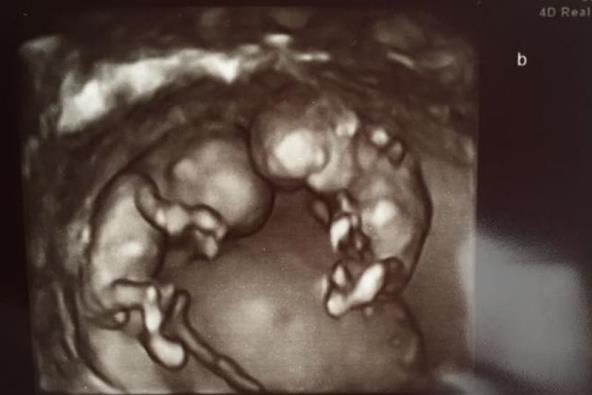

"Videla sam dva dečaka nekoliko dana ranije na ultra zvuku. Ritali su se, a otkucaji srca su bili normalni", rekla je Žaklin za roditeljski portal Popsugar. "Nije bilo nikakvih indikacija da će se završiti tako kako se završilo", dodala je.

Čim su otkrili pol, par je odlučio da se dečaci, identični blizanci, zovu Vilijam i Henri. I sa njih dvojicom sve je bilo uredu do tog dana...